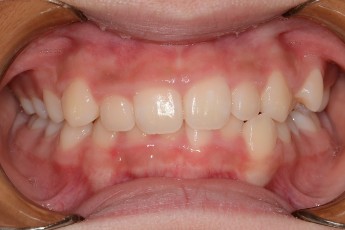

Before

After